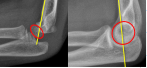

Q what is the left angle of this radiograph? and what is the average + range?

A: Tibial Angle (Ankle)

assesses the medial angle between the medial malleolus and the talus lines. The average is 53°, with a range of 45-65°.

Q what is the right angle of this radiograph? and what is the average + range?

A: Fibular Angle

assesses the lateral angle between the lateral malleolus and the talus lines. The average is 52°, with a range of 43-63°.